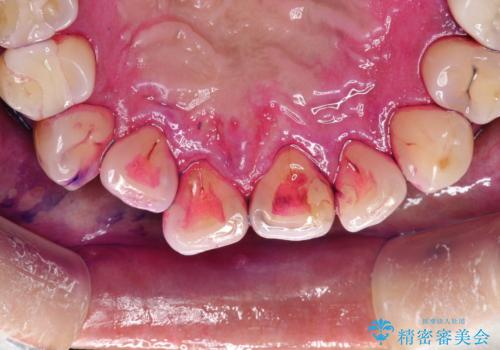

- 半年ぶりの来院できれいにクリーニンングしてほしいとのことでした。染め出しをして歯磨きチェックとPMTC30分コースを行いました。

歯の染め出しとは、汚れがついている部分に色が着いて、どの部分が磨けていないか分かりやすく確認することができます。歯の表面についているプラークは歯と同じ色をしているので見た目では分かりにくいものです。そのため、染め出しをすると、長い期間付着している汚れが濃い色になったり、どの部分が苦手で磨き残してしまっているか確認することが出来ます。